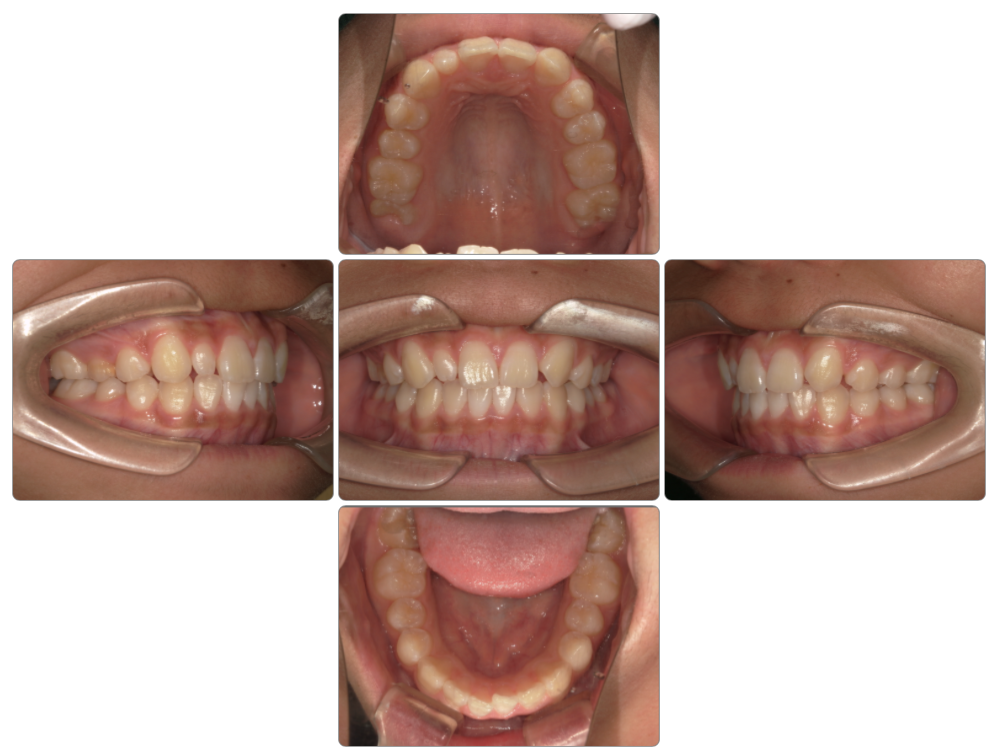

Before

after

| 初診時 | 8歳0ヵ月 |

| 治療期間 | 1年半 |

| 費用 | ¥550,000・調整料 ¥5,500/月 |

| 使用装置 | マイオブレイス・BBI・BWS |

| リスクと副作用 | |

| 原因と考察 | 顎の上がった姿勢になっており舌が前歯の裏側にまで届いていません。ここに丸飲み習慣が重なり前歯が後ろに倒されています。体幹指導と共に丸飲みにならないための食生活指導が必要です。 |